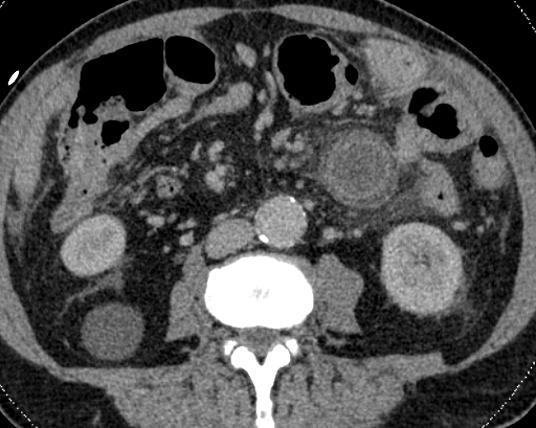

Een 74-jarige man heeft sinds twee dagen acute pijnklachten aan de linkerkant van zijn buik. Sinds een jaar heeft hij moeizame ontlasting en rectaal bloedverlies.